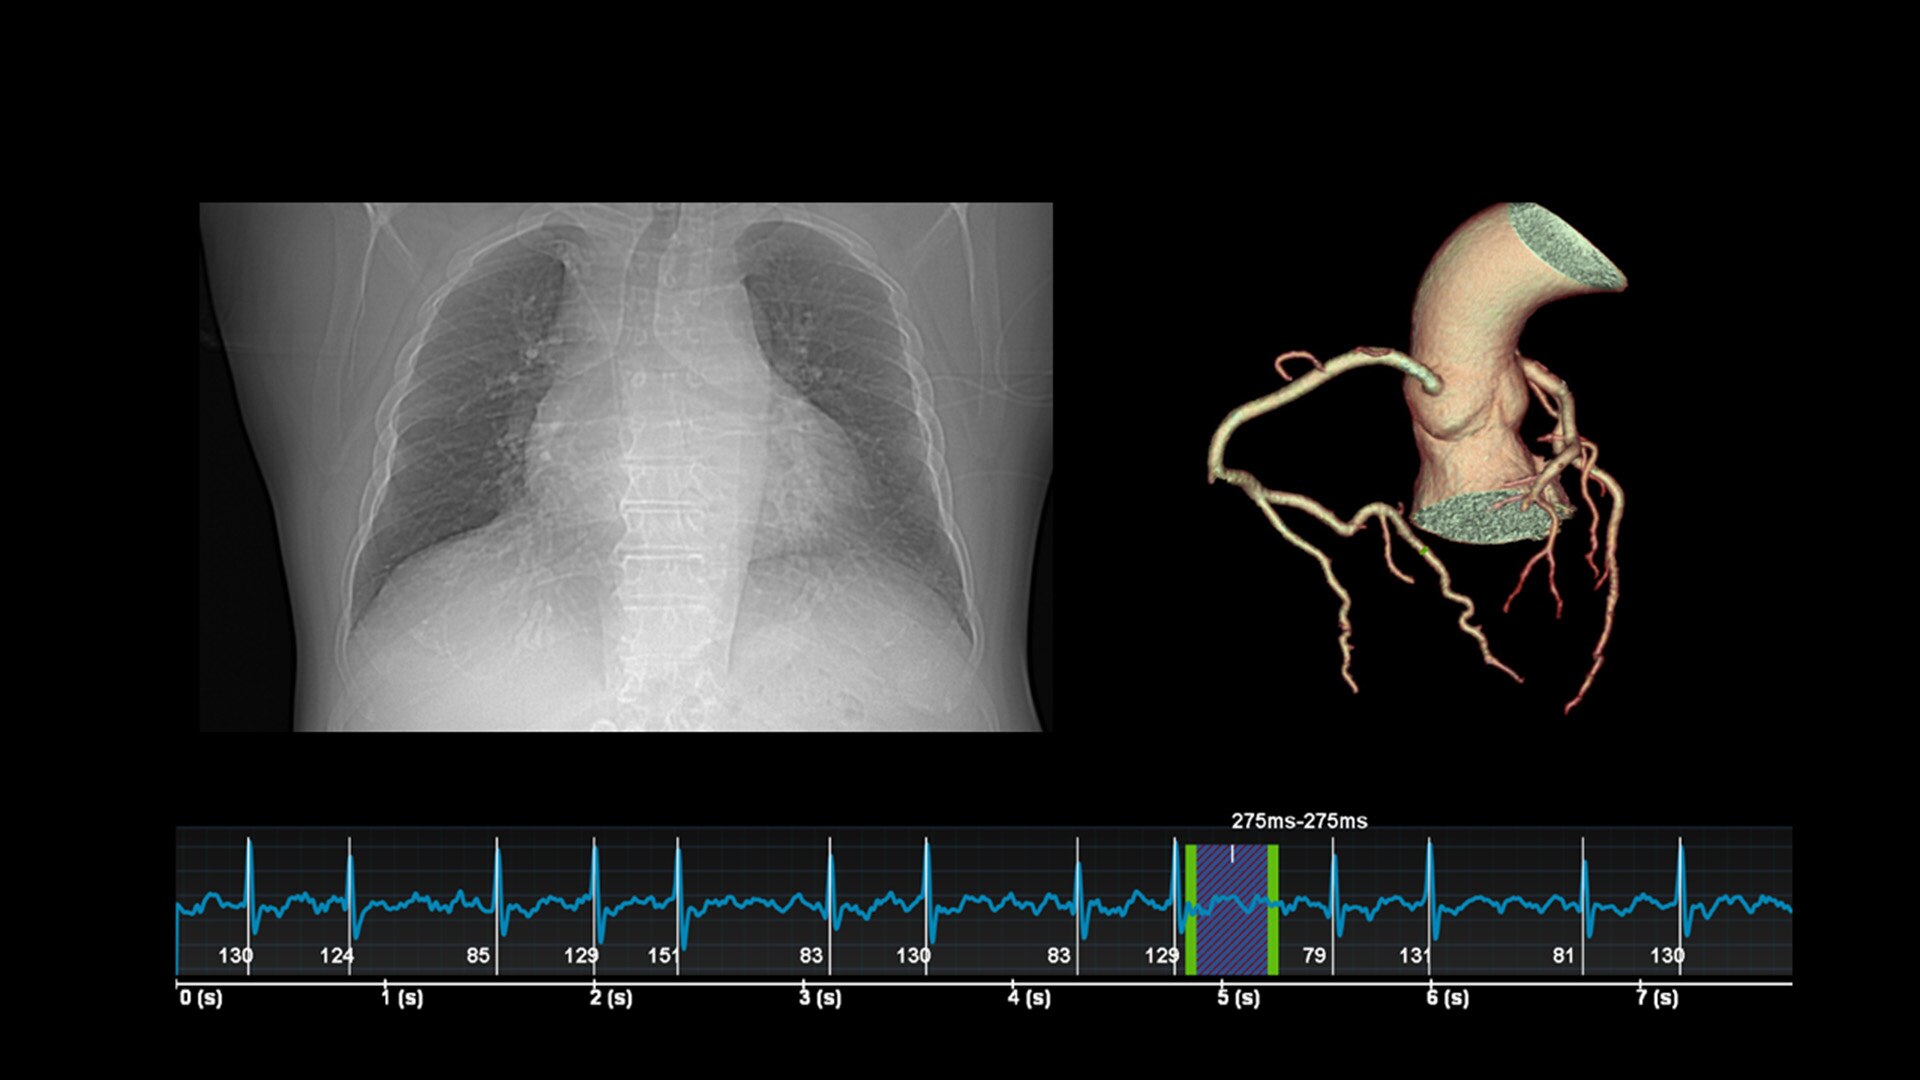

HD-Flow™

Función Doppler bidireccional que reduce la sobrescritura y aumenta la sensibilidad en comparación con el Doppler en color convencional.

Tecnologías HD Live

Utilice una combinación de técnicas avanzadas de iluminación y oscurecimiento de la piel para mostrar imágenes con una profundidad y claridad sin precedentes.